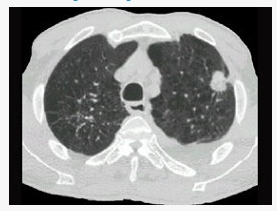

女,64岁,胸背疼痛一周,CT检查如图,最可能的诊断为()

A . 左上肺结核球

B . 左上肺周围型肺癌

C . 左上肺炎性假瘤

D . 左上肺单发性转移癌

E . 左上肺错构瘤